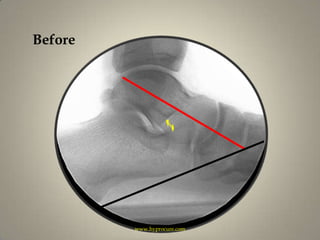

Beforewww.hyprocure.com

HyProCured™www.hyprocure.com